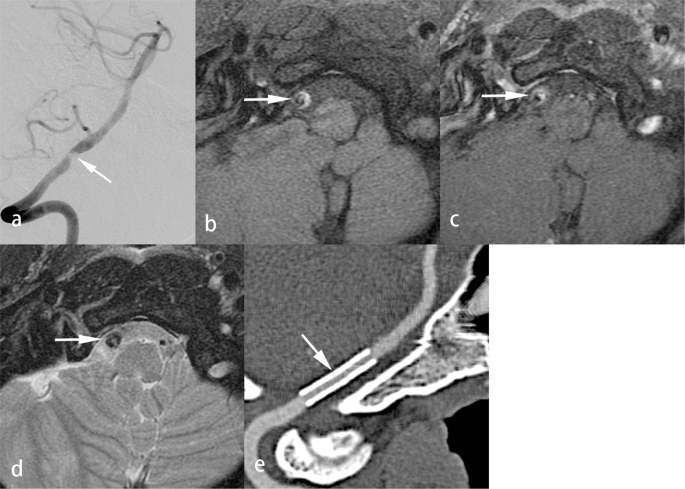

Atherosclerotic disease is the most common cause of intracranial arterial stenosis. The clinical significance of VW-MRI findings in atherosclerosis has been described1,21,22. Dissection is a common etiology of VBS23,24 and an etiology of stroke, where it is more frequent in the posterior circulation territory than in the anterior circulation territory25. We correlated SLR with clinical and MR findings and proposed DA as a new diagnostic category (Fig. 1, Table 3). This new diagnosis applies to patients with stenotic lesions of mixed pathology in which the dissection occurs in a segment of stenosis caused by atherosclerosis. For DA, atherosclerotic plaques and an intramural hematoma in association with intimal surface injury are evident on VW-MRI or angiogram (Fig. 1). Intramural hematoma can be differentiated from intra-plaque hemorrhage by being localized within a plaque and not by being associated with intimal surface injury. Clinical history and symptoms of dissection, such as previous trauma, headache and neck pain, were found in our patients with DA. In Table 3, the clinical and MR findings were not significantly different between the DA group and dissection group. However, hard lesions were significantly more frequent in the DA group than the dissection group. This suggests that the signals of intramural hematomas in the DA and dissection groups were very similar on VW-MRI. Without a comprehensive neurological and neuroradiological evaluation, DA may be diagnosed as dissection, possibly delaying the process of stroke prevention.

The other clinical justifications for DA as a new disease entity include the following: (1) The complex pathology of DA may influence the temporal signal change of intramural hematomas at the dissection level on VW-MRI. The pathological status of plaques can change the process of regression and resorption of the adjacent intramural hematoma. Thus, the temporal change in signal intensity of the stenotic lesion in DA is not that of the stenotic lesion in dissection or atherosclerosis. For example, a chronic, unhealed dissection occurring in an inflammatory plaque may show low intensity signals on T1WI and enhancement after contrast injection on VW-MRI (Fig. 1). (2) Patients with DA have different outcomes from patients with dissection after endovascular management. Though not statistically significant in the present study, residual stenosis and ISR trended higher in the DA group than in the dissection group. Differentiating DA from dissection may help interventionists evaluate outcome. (3) Medical treatment outcomes differ between patients with DA and patients with dissection. The outcomes of medical treatment for dissection were worse in patients with neurovascular atherosclerosis than in patients without atherosclerosis4.